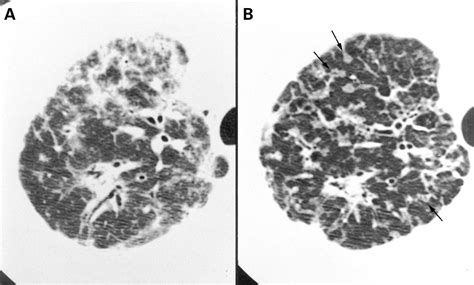

Once the scan is completed, a radiologist will interpret the images and generate a report. When viewing a Pneumonia CT Scan, medical professionals look for specific patterns of lung involvement. These patterns often indicate the type of pneumonia or the severity of the inflammatory response.

Common findings often described in reports include:

• Consolidation: This refers to the filling of air spaces (alveoli) with fluid, pus, or other material, appearing as dense, white areas on the scan.

• Ground-Glass Opacity (GGO): A hazy appearance in the lungs, indicating partial filling of air spaces or thickening of the lung interstitium. This is often seen in viral pneumonias.

• Bronchograms: The appearance of air-filled bronchi surrounded by consolidated lung tissue.

• Pleural Effusion: The buildup of fluid in the space between the lung and the chest wall.

• Nodules or Cavitation: These findings may prompt further investigation to rule out other infections or malignancy.

It is important to remember that these findings must always be correlated with the patient's symptoms, laboratory results, and clinical history. A report with "positive findings" does not always imply a worst-case scenario, as many patterns are typical of common bacterial or viral infections.